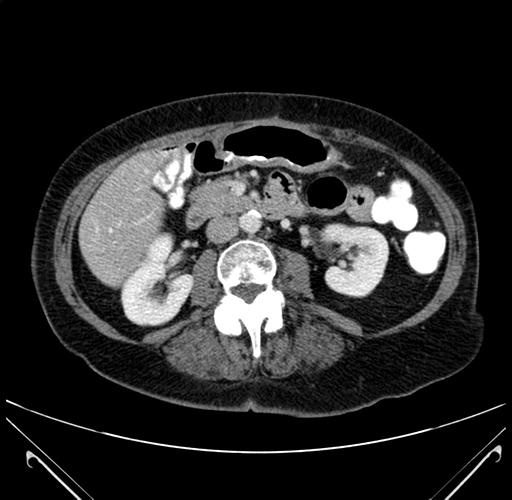

Pre-Chemo: Axial Venous

Axial Venous